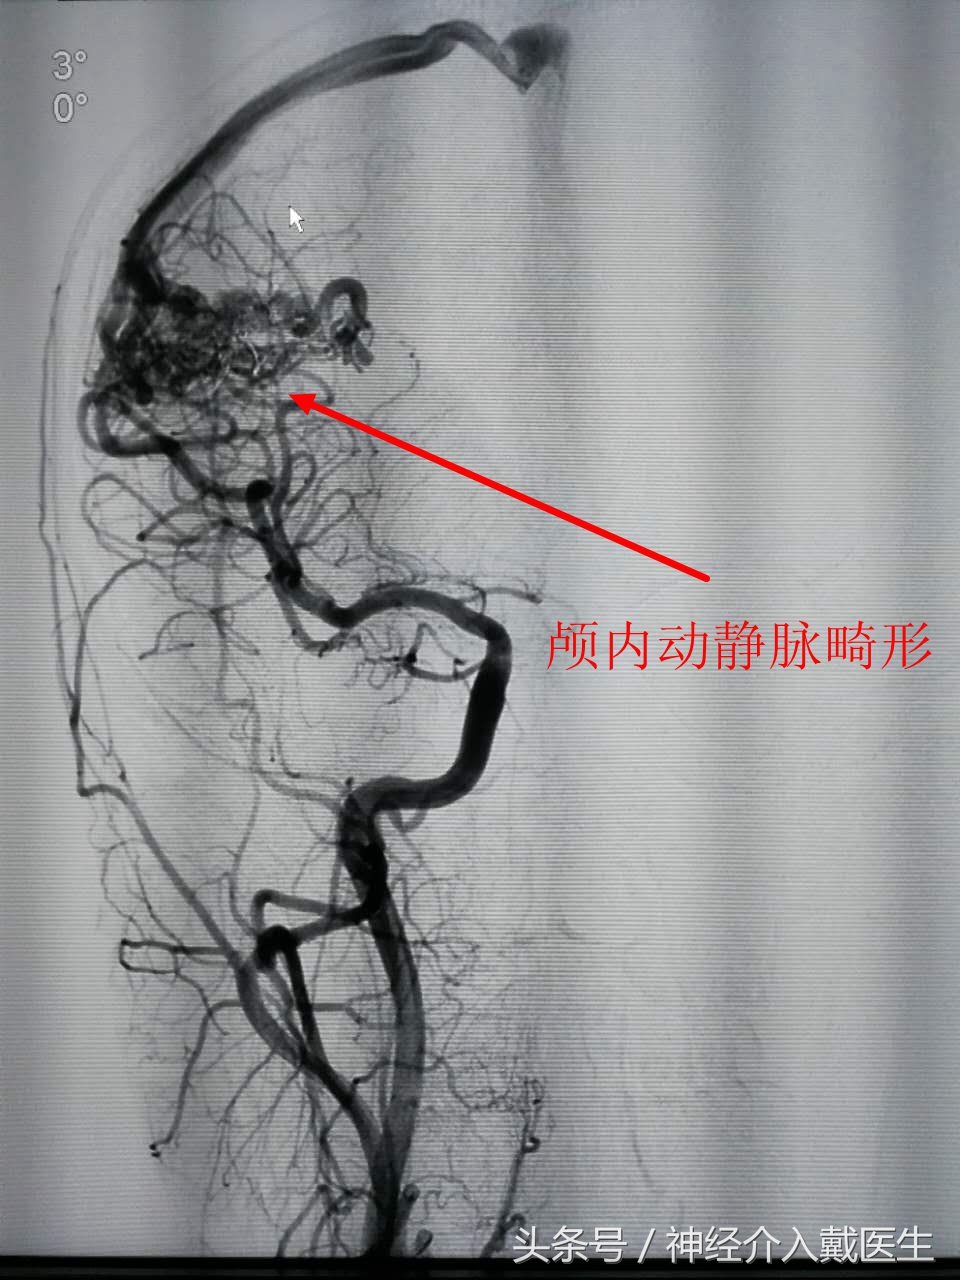

脑血管疾病一般一般都需要通过做脑血管造影(DSA),来明确病因,比如蛛网膜下腔出血,一定要脑血管造影明确是否有颅内动脉瘤,怀疑颅内血管畸形更加需要通过脑血管造影才能明确颅内动静脉畸形。总之脑血管造影是诊断脑血管疾病的金标准,

颅内出血,发生这样的并发症主要颅内本身存在病变血管,比如颅内动脉瘤,脑血管畸形,动脉粥样硬化,术中血压太高,发生出血的风险较大,能够预防出血的最重要的办法就是控制术中血压,对导丝,导管的操作要细腻。